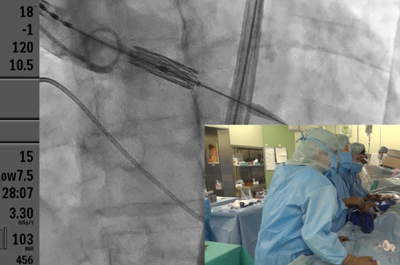

大動脈弁狭窄症に対する経カテーテル大動脈弁置換(TAVR TAVI)といった低侵襲治療にも取り組んでいます。従来であれば、併存疾患や高齢などの理由で治療が不可能とされていた患者さんにも治療の道が開かれた形となり、当院での治療例数も大きく増加しています。僧帽弁閉鎖不全症に対するMitraclip、心房中隔欠損症(ASD)や動脈管開存(PDA)に対するカテーテル閉鎖など、構造的心疾患(SHD)といわれる分野のカテーテル治療は、昨今急速展開している分野です。低侵襲治療TAVI ハートチームのページはこちら